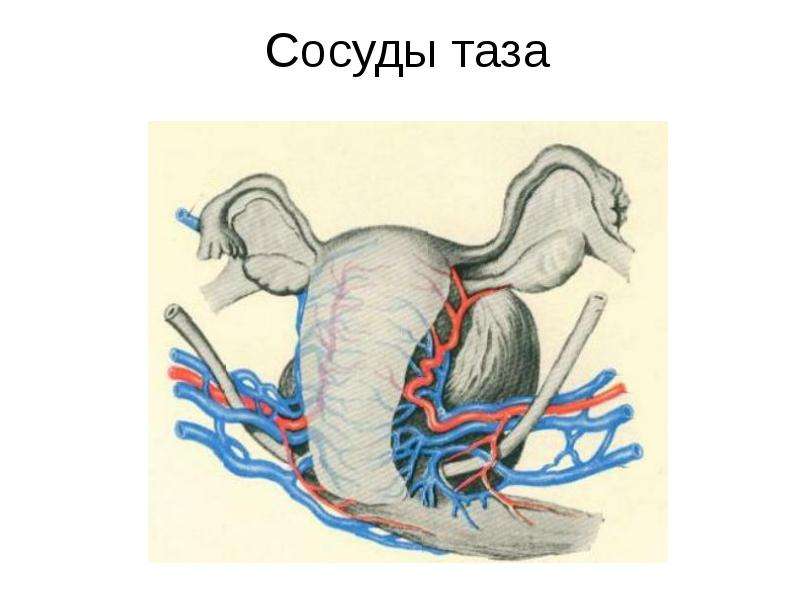

Анатомия малого таза: детальные схемы и изображения